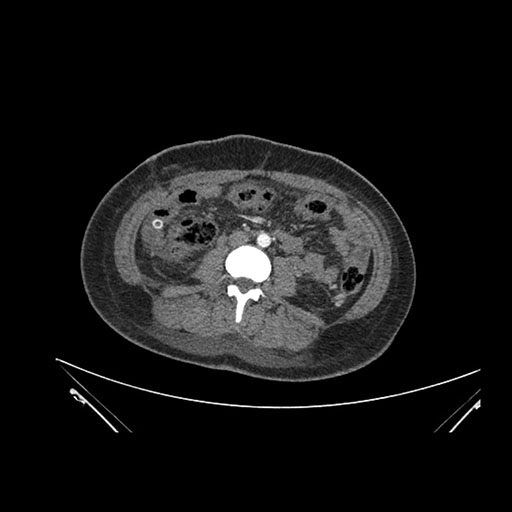

Imaging Analysis

Look through the patient's CT scan to identify any areas of concern for the necessary procedure.

Coronal Venous

Based on initial findings, which issue(s) would you be most concerned about?